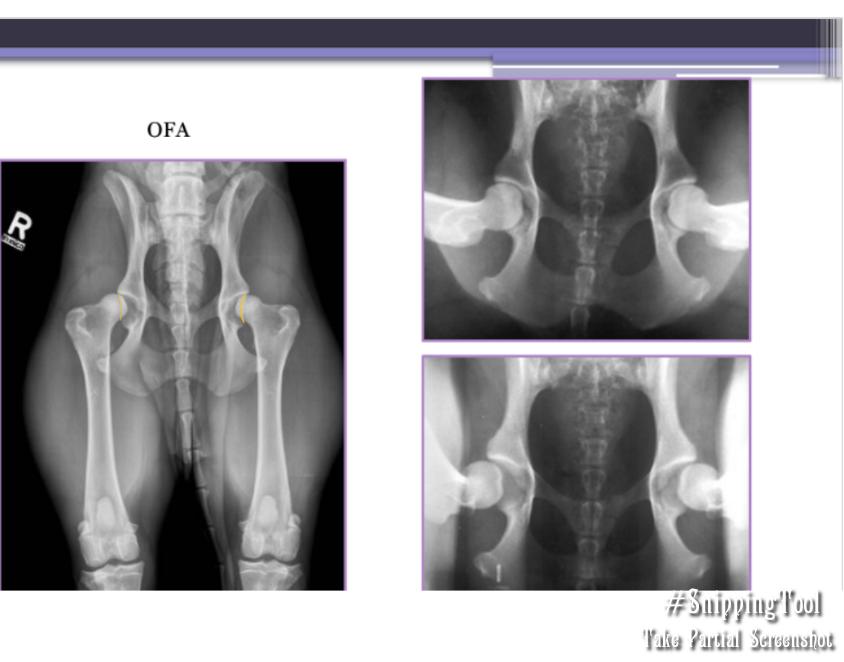

Screening for Hip Displasia

OFA: Evaluates passive laxity

When: Certified >2 years

Grades:

Normal: excellent, good, fair, borderline

Dysplastic: mild, moderate, severe

PennHip: Evaluates passive distractive laxity

When: Certified >16 weeks

Grades: Scale 0–1

0.58 = 58% femoral head displacement

Diagnostic Imaging for Hip Dysplasia

VD most useful

Want >50% acetabular coverage!

Rads: Bone shape, remodeling, osteophytosis(neck), enthesiophytosis (Morgan’s line), laxity

Do not treat the radiograph!